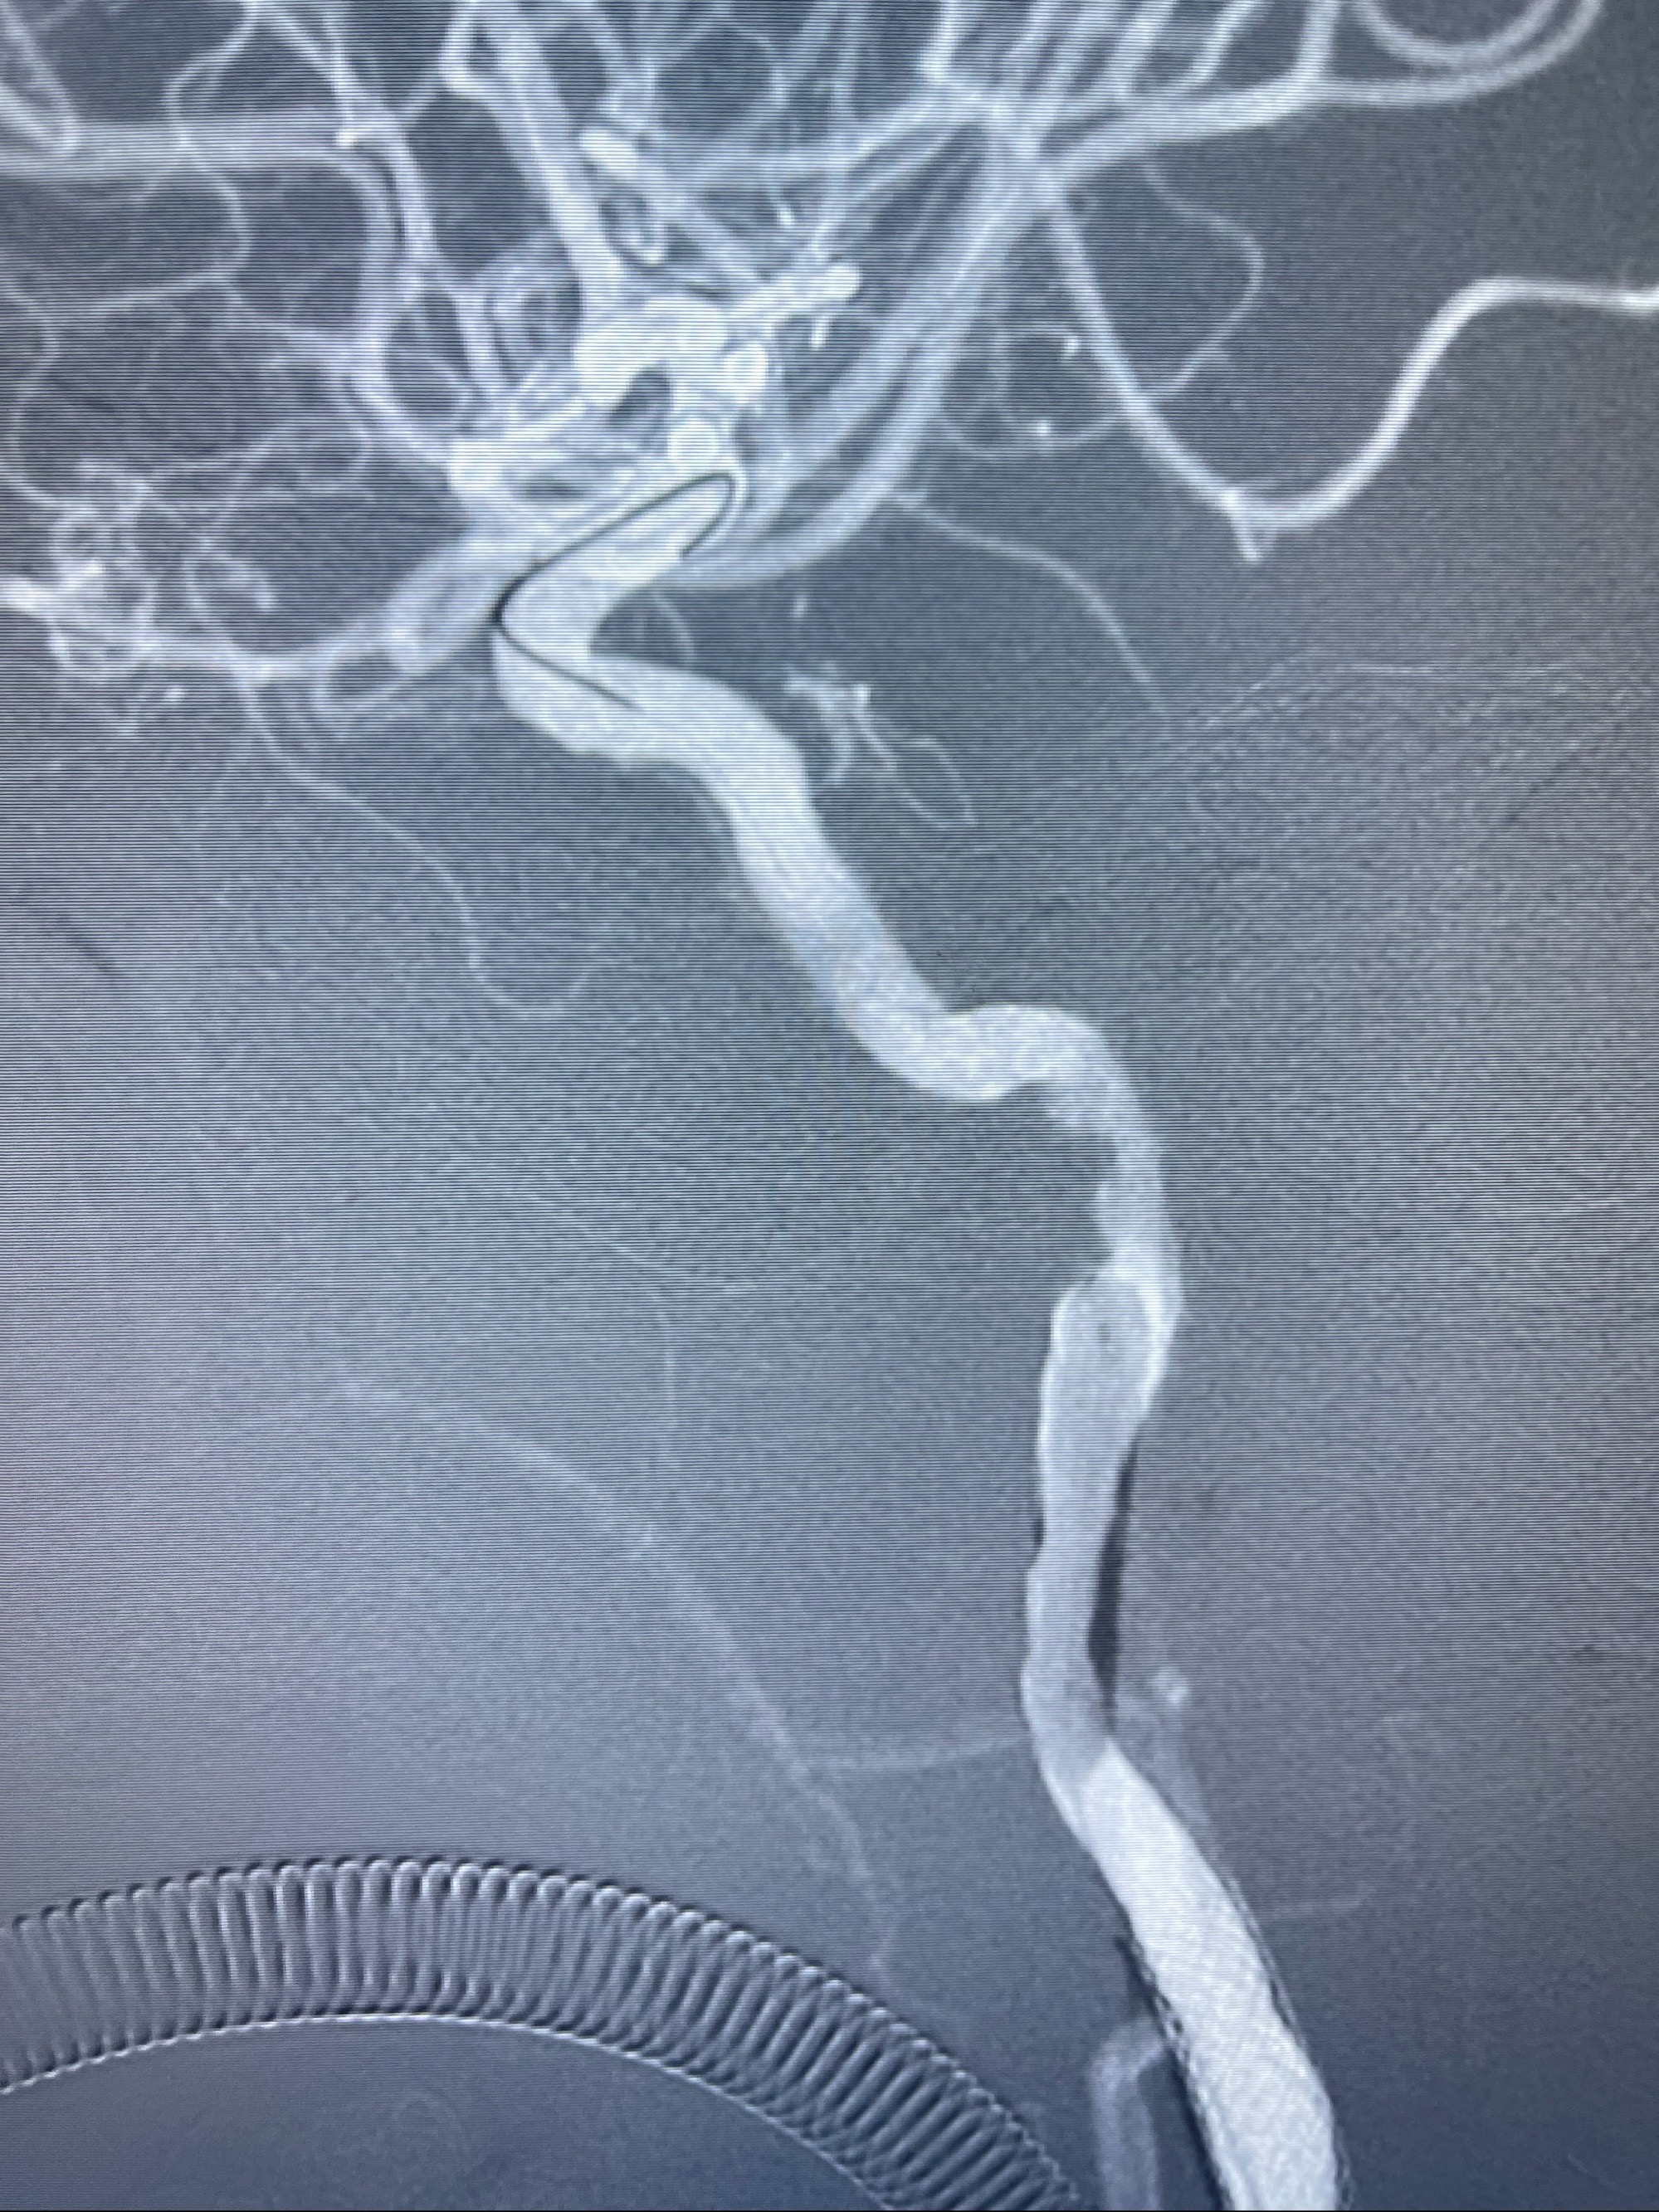

右侧椎动脉可见吻合代偿右侧颈外动脉

左侧颈总动脉起始段至分叉部闭塞,起始部呈现子弹头样改变

左侧椎动脉可见代偿显示左侧前循环